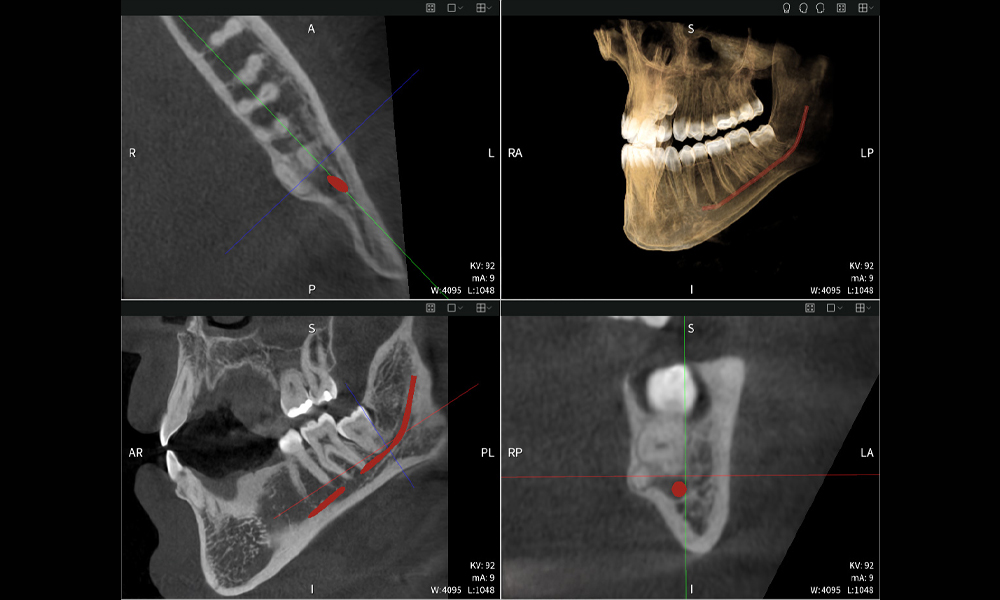

A continuación encontrarás un caso del Dr. med. dent. Oliver A. Centrella, en el cual las imágenes CBCT obtenidas con Seethrough Max proporcionaron información crucial sobre la anatomía compleja y la relación crítica entre las muelas del juicio y el nervio alveolar inferior. En este caso, existe una indicación para la extracción quirúrgica de las muelas del juicio.

• Arriba a la izquierda: Corte axial de la mandíbula izquierda (región 38) que muestra el nervio alveolar inferior (en rojo) en proximidad a las raíces del diente 38.

• Arriba a la derecha: Reconstrucción 3D de toda la mandíbula para orientación. El nervio alveolar inferior marcado en rojo ilustra su ubicación dentro del hueso mandibular.

• Abajo a la izquierda: Vista sagital de la mandíbula (región 38), destacando la estrecha relación espacial entre las raíces y el conducto del nervio.

• Abajo a la derecha: Vista coronal de la mandíbula (región 38), crucial para evaluar la posición espacial de las raíces en relación con el nervio.

Figura b: Resultados de imagen de Seethrough Max, sobre un fondo negro.